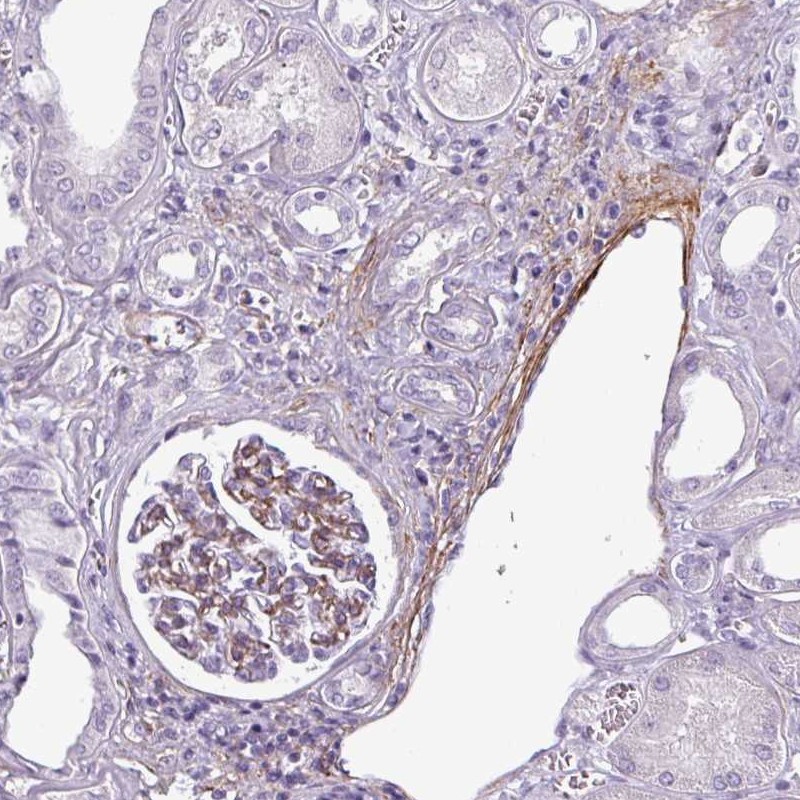

Immunohistochemical staining of human kidney shows moderate cytoplasmic and membranous positivity in cells in glomeruli.